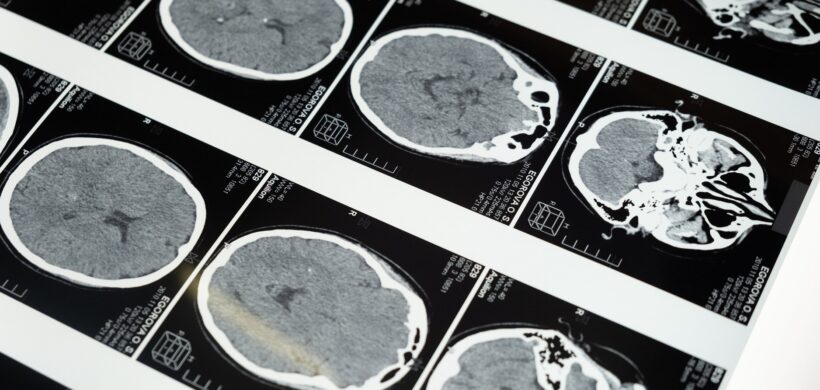

Eje 2: La persona en el centro de la atención sociosanitaria: Prevención, diagnóstico y tratamiento

Categorías: Plan Integral de Alzhéimer

Información relacionada con el Plan Integral de Alzhéimer y otras demencias (2019-2023)